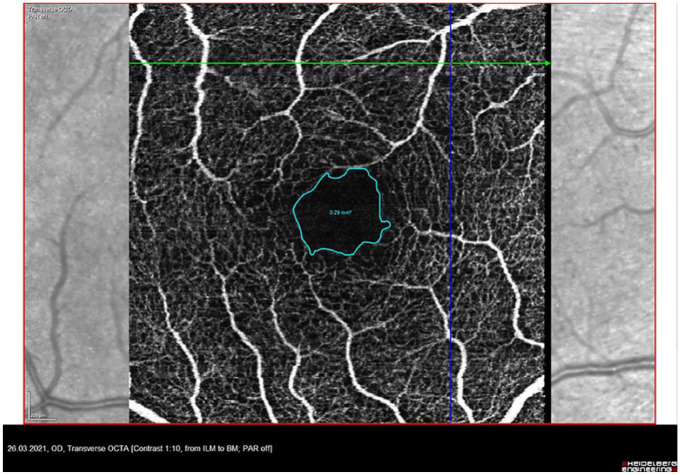

Objectives: We aim to assess relevant differences in vessel density (VD) in Optical Coherence Tomography Angiography (OCTA) in those diseases to use it as an easily available diagnostic tool.

Methods: OCTA (Heidelberg Engineering OCT SPECTRALIS) of the superficial vascular plexus, intermediate capillary plexus (ICP) and deep capillary plexus (DCP) of the retina was prospectively performed in Neuro-Sjögren, age-matched CIDP patients (n = 31, each), and healthy controls (n = 30). Vessel density (VD) and foveal avascular zone (FAZ) was measured with Erlangen Angio Tool.

Results: Significantly lower VD were found for the DCP and ICP in Neuro-Sjögren and CIDP patients compared to healthy controls (p = 0.0002 and <0.0001). When group comparison was age-adjusted, these differences were not found anymore. Different frequencies of "low" retinal blood flow in each layer comparing Neuro-Sjögren and CIDP patients were not found. FAZ revealed no significant differences between patients with Neuro-Sjögren, CIDP and healthy controls.

Conclusion: This study found no significant differences in VD or the foveal avascular zone between Neuro-Sjögren and CIDP patients using OCTA, suggesting that inflammatory vascular changes in the retina are uncommon in Neuro-Sjögren patients.